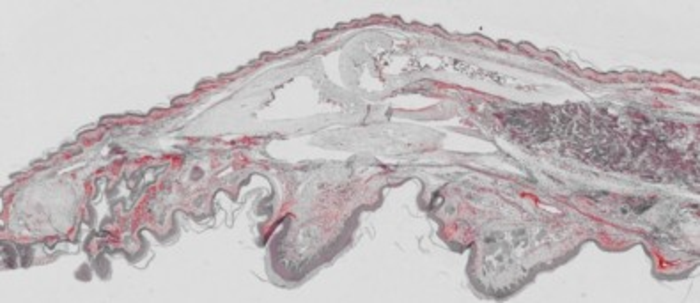

Mayaro-infected mouse paw (red) analyzed by immunohistochemistry

University of São Paulo (USP)